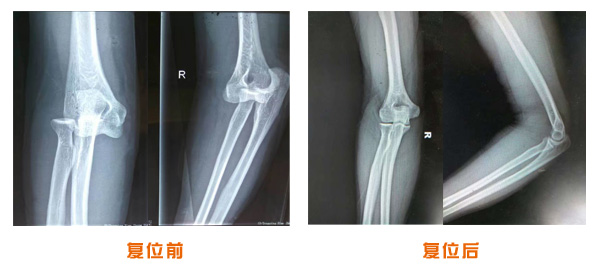

肘關節脫位骨折治療前后對比

復位前后對比